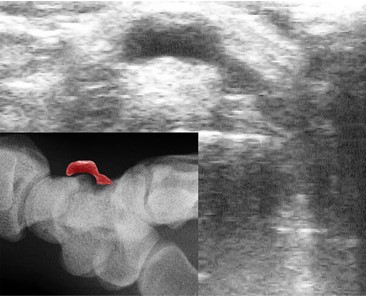

Ο ασθενής με γάγγλιο του καρπού χρειάζεται εκτίμηση από εξειδικευμένο Ορθοπαιδικό Χειρουργό. Ο κ. Βλάχος αφού λάβει το ιστορικό σας και σας εξετάσει πολύ προσεκτικά, θα πραγματοποιήσει υπερηχογράφημα με σκοπό να επιβεβαιώση την διάγνωση. Σε ορισμένες περιπτώσεις θα χρειαστεί η λήψη μιας ακτινογραφίας ώστε να αποκλειστεί το ενδεχόμενο οστεοαρθρίτιδας ή άλλων παθήσεων του καρπού. Σε συγκεκριμένες περιπτώσεις ο ιατρός θα χρειαστεί να σας παραπέμψει για μαγνητική τομογραφία.